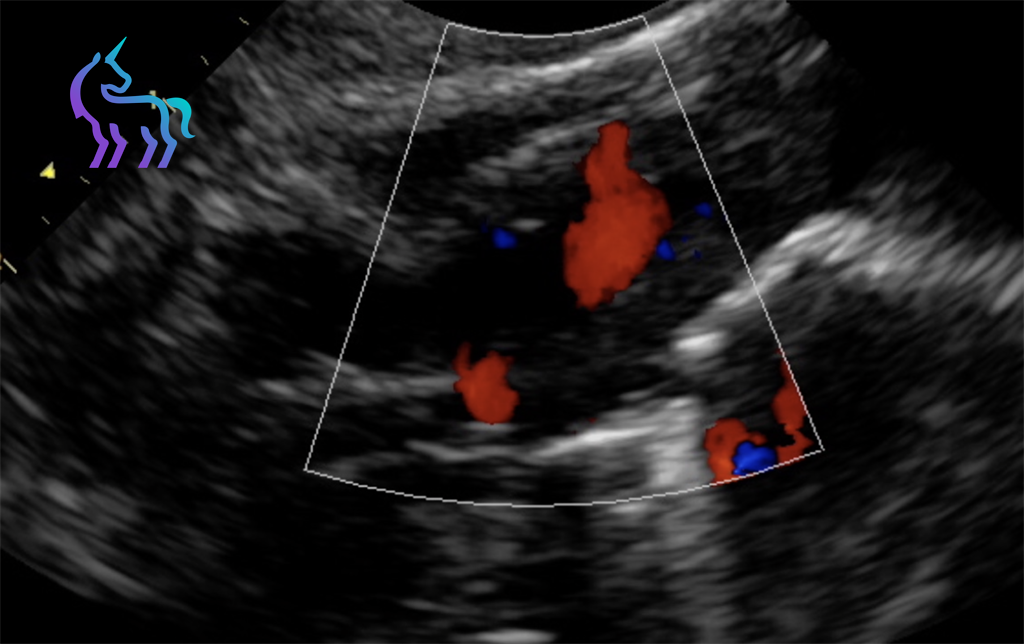

Notre plateau technique intègre les technologies les plus avancées pour une approche diagnostique complète et précise.